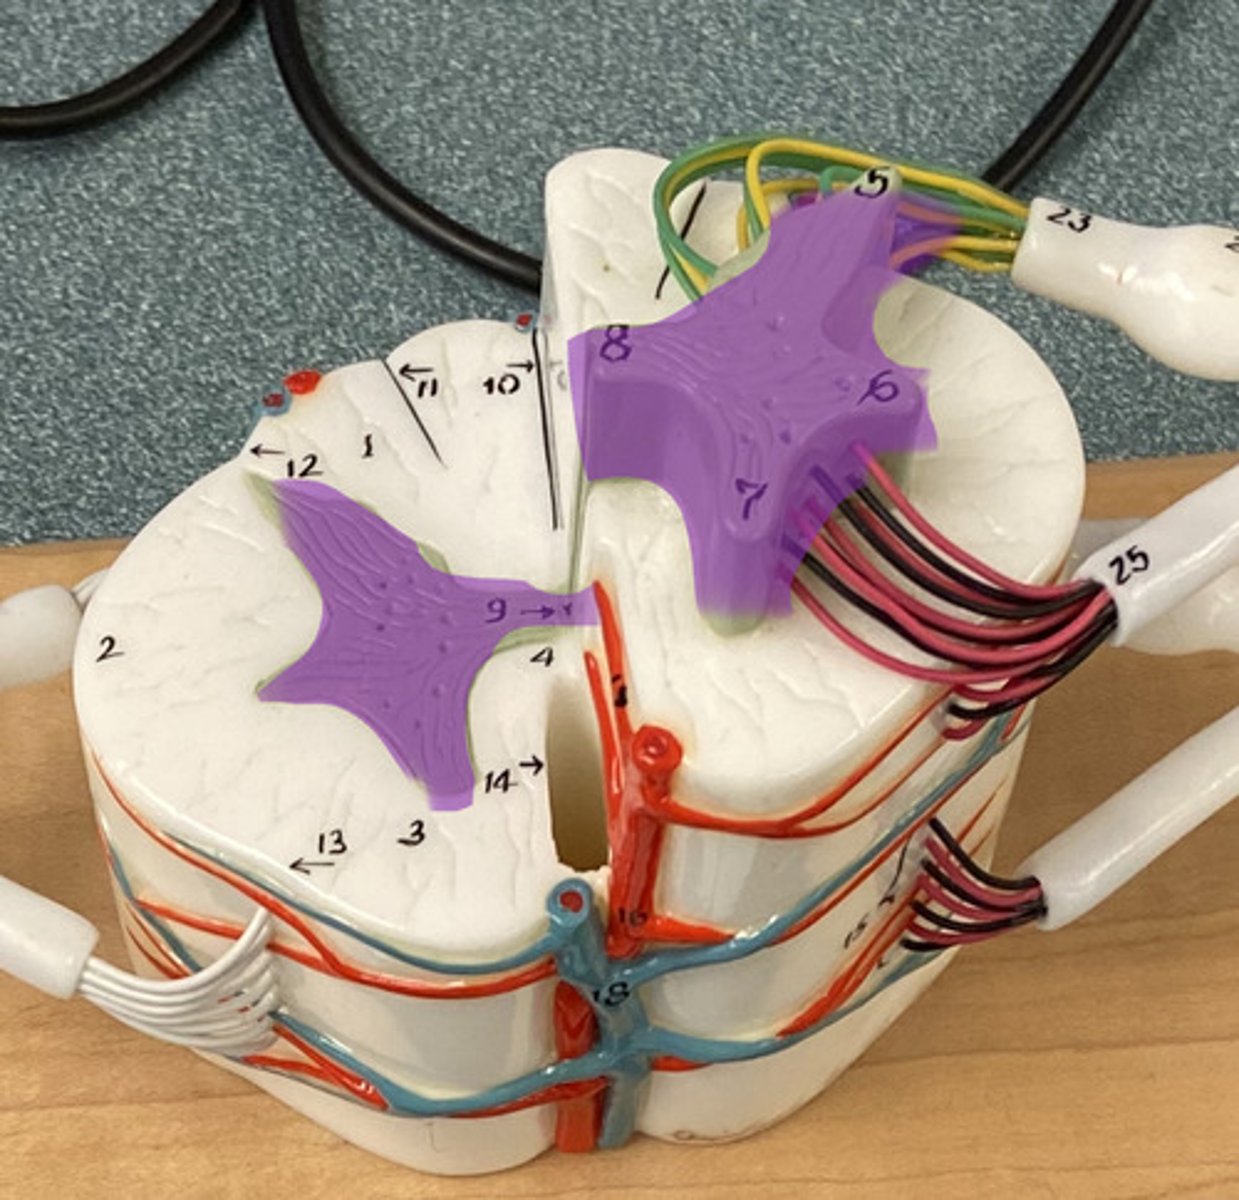

White Columns/ Matter

Gray Matter

Dorsal Horn

Lateral Horn

Dorsal (posterior) Median Sulcus

Ventral (anterior) Median Fissure

Central Canal

Ventral Root

Dorsal Root

Dorsal Root Ganglion